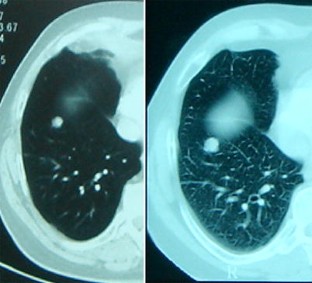

Abb. 2